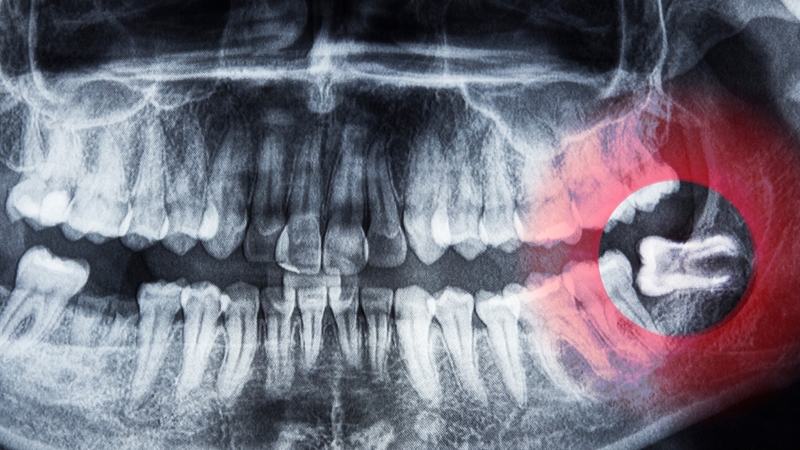

Răng khôn mọc lệch trong xương hàm

Răng khôn mọc lệch trong xương hàm là tình trạng răng khôn bị bao phủ hoàn toàn bởi xương hàm, không có biểu hiện lâm sàng rõ rệt. Thông thường, nó chỉ được phát hiện tình cờ qua hình ảnh X-quang. Dù không gây triệu chứng ngay lập tức, nhưng về lâu dài có thể dẫn đến:

• Hình thành u nang quanh thân răng (dentigerous cyst).

• Tiêu xương vùng lân cận hoặc thay đổi hình dạng xương hàm.

Răng khôn mọc lệch trong xương hàm là tình trạng răng khôn bị bao phủ hoàn toàn bởi xương hàm